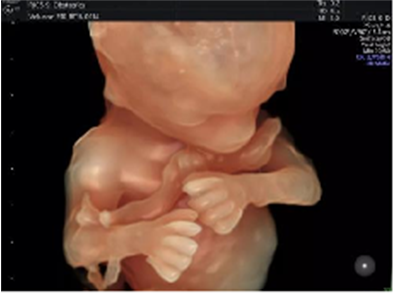

安琪兒超聲儀作為美國(guó)GE四維彩超,是目前先進(jìn)的彩色超聲設(shè)備,是篩查胎兒畸形的高端設(shè)備。

四維彩超成熟的煊光、煊影、煊流成像技術(shù),通過(guò)細(xì)致的多切面成像分析胎兒的解剖結(jié)構(gòu)及發(fā)育狀況能夠提供更多圖像數(shù)據(jù),可以更加清晰、完整的記錄胎兒宮內(nèi)的高清動(dòng)態(tài)。

獨(dú)有的表面模式、血管模式、組織血管透明模式等智能診斷模式,對(duì)胎兒的體表、內(nèi)臟、血管、骨骼等九大核心部位獨(dú)立成像,彌補(bǔ)傳統(tǒng)系統(tǒng)、四維彩超在檢測(cè)范疇及精準(zhǔn)度的局限性。